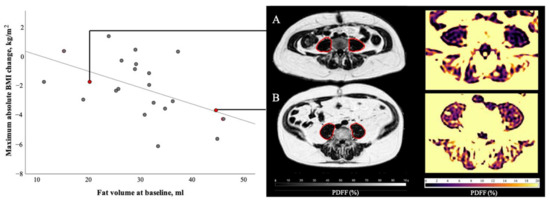

Manual segmentation was performed on the water-separated images merged over the four stacks. Psoas and erector spinae muscle were segmented using the polygon-tool in the free open-source software ITK-SNAP [28] (www.itksnap.org, accessed on 3 February 2020). Reliability of the manual segmentation was ensured by defining the target area precisely and reviewing the segmentation with a board certified radiologist (7 years of experience in whole-body imaging). Psoas muscle was segmented bilaterally from its origin to the myotendinous junction at the height of the acetabulum. Erector spinae muscle included M. iliocostalis, Mm. intertransversarii, Mm. levatores costarum, Mm. interspinales, Mm. rotatores breves and longi, M. multifidus and M. semispinalis. Erector spinae muscle was segmented bilaterally from the height of the liver dome to its most caudal insertion at the Os sacrum. A representative muscle segmentation is displayed in Figure 1. In order to exclude unintentionally included bony structures, an automated post processing step removed voxels with T2* values below 5 ms and above 100 ms from the PDFF analysis (Python version 2.7; https://www.python.org/, accessed on 6 April 2020).

Figure 1.

Representative segmentation of psoas (1) and erector spinae (2) muscle shown in the PDFF map at the level of the fourth lumbar vertebra (L4). The subject is a 60-year-old male with a BMI of 26.0 kg/m2 suffering from ductal adenocarcinoma of the pancreas.